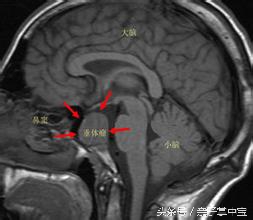

她遵照医嘱做了核磁共振,检查结果让人大吃一惊,冯小姐的颅内竟有一个直径2厘米左右的脑垂体瘤。

这种脑垂体瘤就是导致冯女士久婚不孕的罪魁祸首,其实这种瘤是一种常见的颅内肿瘤,发病比例为1比10万,但近年来有增长趋势,大多发生在育龄妇女身上。

脑垂体瘤患者体内内分泌、性激素水平出现异常,导致久婚不孕不育的情况,患者还可能会出现视力下降、体毛减少、肢端肥大等情况。